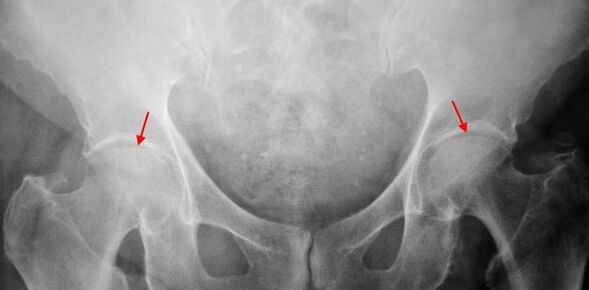

In X -ray images for coxarthrosis of the 2nd degree, significant uneven narrowing of the joint gap (more than half from normal height) is determined.The femoral head is somewhat shifted upward, deformed and increases in size, and its contours become uneven.Bone growths with this degree of coxarthrosis appear not only on the internal, but also on the outer edge of the acetabulum and go outside the cartilage.

The diagnosis of coxarthrosis is based on clinical signs and data of additional studies, the main of which is radiography.In many cases, x -rays make it possible to establish not only the degree of coxarthrosis, but also the cause of its occurrence.So, for example, an increase in the neck-diaphyseal angle, the scenes and flattening of the acetabulum indicate dysplasia, and changes in the shape of the proximal part of the femur are indicated that coksartrosis is a consequence of Pertes's disease or youthful epiphysiolysis.On radiographs of patients with coxarthrosis, changes can also be detected indicating injuries.